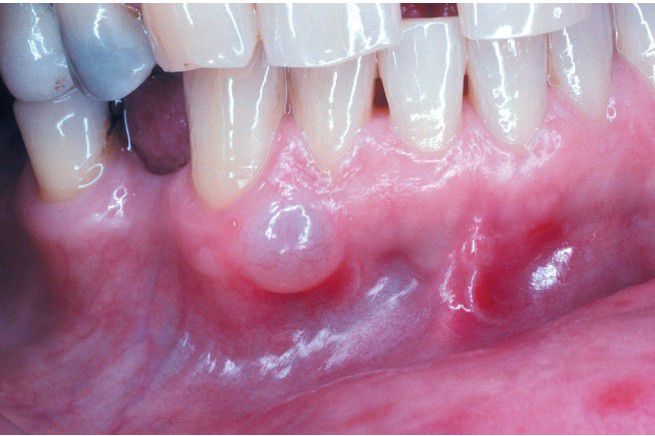

Gingival Cyst of the Adult

. Tense, fluid-filled swelling on the facial gingiva.